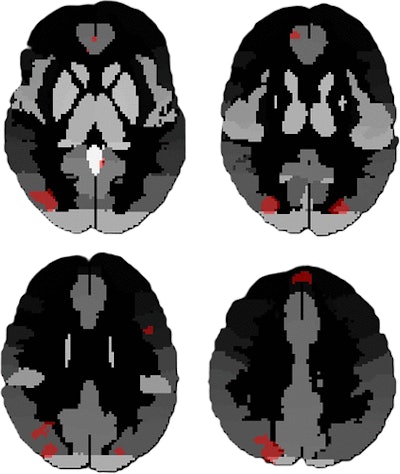

Functional MRI (fMRI) scans depict the merged regions of interest that showed significant differences between the two datasets of high and low blast exposure groups. The clusters involved the bilateral superior and inferior lateral occipital cortex, the frontal medial cortex, left superior frontal gyrus, and precuneus. Image courtesy of the RSNA.

From the final cohort of 212, those with higher blast exposure showed differences in functional connectivity in the superior and inferior lateral occipital cortex (LOC), frontal medial cortex, left superior frontal gyrus, and precuneus (p = 0.001 to 0.04), compared with the low-exposure group, the authors noted.

Participants with higher exposure to significant explosives showed increased volume in the left and right superolateral occipital cortices. In particular, the higher large explosive exposure group in dataset 1 (n = 161) showed significantly greater volumes in the right superior LOC compared to the lower-exposure group (19,431 mm3 ± 210.0 vs. 19,166 mm3 ± 190.4, respectively; p = 0.016) and in the left superior LOC compared with the lower exposure group (19,550 mm3 ± 209.0 vs. 18,911 mm3 ± 187.7; p = 0.018).

The high-exposure group also scored higher on the Neurobehavioral Symptom Inventory and Posttraumatic Stress Disorder Checklist for the Diagnostic and Statistical Manual of Mental Disorders. Clinical scores from both were inversely correlated with FC in regions linked to cognition, attention, and emotional regulation, including the LOC, superior parietal lobule, precuneus, and default mode networks (r = −0.163 to −0.384; p < 0.001 to 0.04), the team reported.